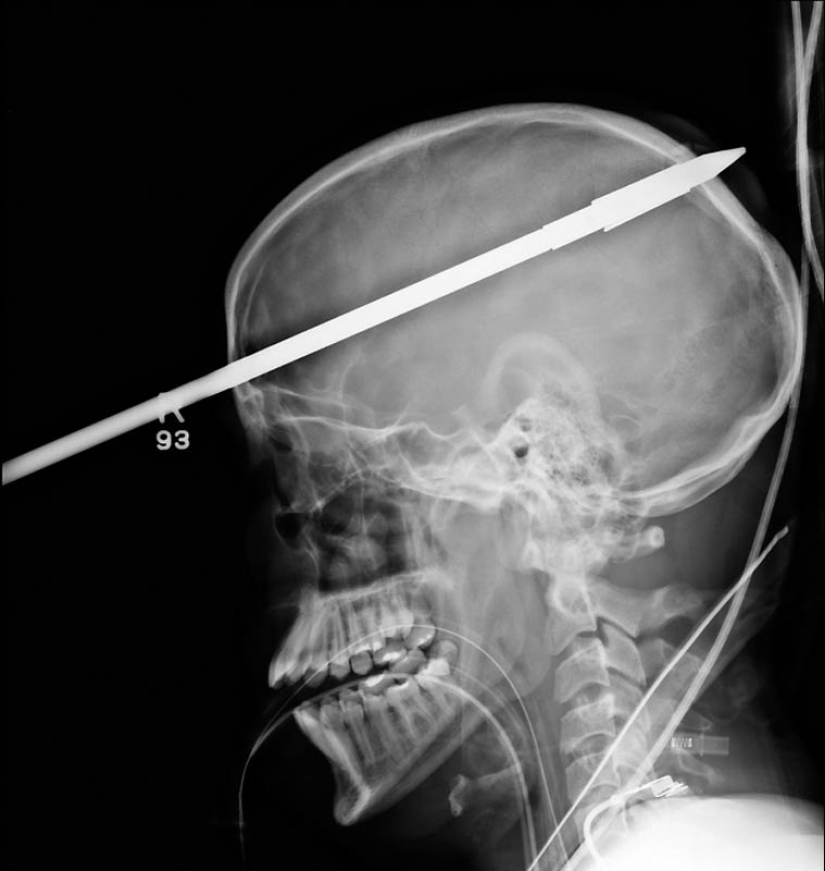

11. A spear from a harpoon that hit a 16-year-old boy in the head on a fishing trip.